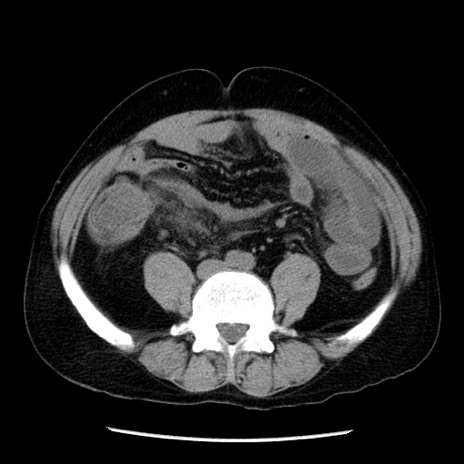

症例29(横断像)

【症例】40歳代男性

【現病歴】2日前から胃痛あり。徐々に周期的な激痛に変化した。本日になっても激痛があるため受診。

【身体所見】意識清明、BT 38-39℃台あり、腹部:膨満、やや硬、右下腹部に圧痛あり。

【データ】WBC 8500、CRP 23.26